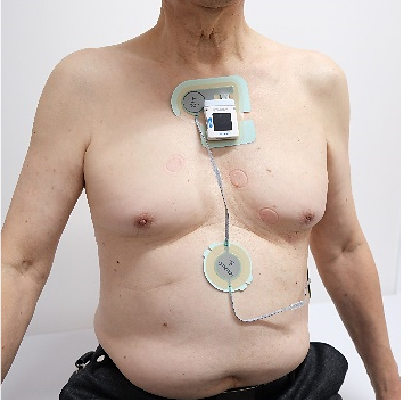

4.ホルター心電図検査(24時間心電図検査)

24時間にわたって日常生活の中での心電図を記録する長時間心電計を使った検査です。通常はこの検査装置の基本を作ったHolter博士の名前をとり、ホルター心電図と呼ばれています。ホルター心電図は長時間にわたって、睡眠中や運動中など日常生活の心電図が記録できるので、不整脈や狭心症の発作時の心電図をとらえることができ、症状の原因診断に役立ちます。動悸や胸の痛みや圧迫感、違和感などがある患者さんには必須の検査です。

胸に5ヵ所ほど電極と小さい記録器を付けます。装着には約15分程度かかります。24時間記録しますが、検査中は運動や飲酒を含めいつも通りの生活を行ってください。じっとしていては、普段の生活の中での心電図の変化が記録できません。お風呂には入れませんので、検査日の前日に入っておいてください。電極が剥がれない程度に軽くシャワーを浴びるのは可能です。また、検査中の出来事や動悸などの症状、就寝、起床、食事、排尿、排便、飲酒などは、装着時に渡される日誌にご記入ください。絆創膏などでかぶれる人は、あらかじめ塗り薬を使う場合がありますのでお申し出ください。装着してから24時間後に外しますがかかる時間は5分程度です。結果が出るまでに1週間~10日程かかります。 -

5.イベント心電図・携帯型心電計

イベント心電図とは、症状がいつどこで起こるかわからない場合に、携帯用心電計を用いて心電図を記録する検査です。不整脈や心筋虚血の診断に役立ち、特に24時間程度と記録時間に制約のあるホルター心電図と並ぶ頻度で使用されています。つまり、毎日起こる症状ならホルター心電図で捕らえることができますが、週に1回しか起こらない症状の場合、ホルター心電図で捉えることができるかどうかわかりません。そこでイベント心電計を使うことになります。電極と記録器を体に装着して頂き、症状が発生したときに記録器のスイッチを押すと、約30秒さかのぼった時点からの心電図が記録されるものや(イベント心電計)、症状が出たときに自分で胸に記録器をあてて心電図を記録するタイプのもの(携帯型心電計)があります。これらの心電計は、ホルター心電図が連続した24時間の心電図のモニターであるのに対し、症状をターゲットとした長期間にわたる非連続心電図モニターです。

電極装着型では数日から1週間程度電極をつけっぱなしになりますので、かぶれやすい人はお申し出ください。症状が出たときに記録する携帯型心電計は、あらかじめ何も症状がないときの心電図を記録しておき、症状が出たら同じ位置にあてて心電図を記録することが重要です。その際、力を入れすぎると手の筋肉から出る電気が邪魔をしますので、優しくそっと胸に当たるようにします。 -